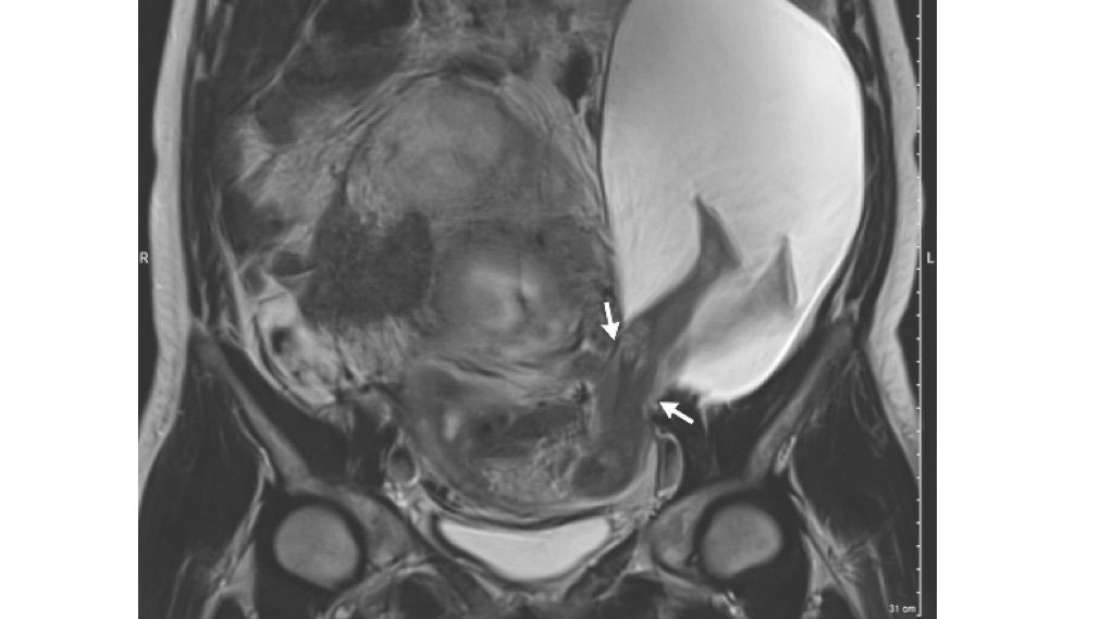

O bebê, às 25 semanas de gestação, causou um rompimento no útero da mãe, esticando suas pernas para a cavidade abdominal. Uma ressonância magnética posterior mostrou que o útero sofreu uma ruptura de 2,5 centímetros. Estimativas mostram que apenas 0,5% de todos os casos de gravidez podem apresentar essa eventualidade.

Esse tipo de ruptura pode ter graves consequências, levando-se em consideração a proximidade do bebê de órgãos vitais da mãe. Apesar disso, todavia, 5 semanas após o diagnóstico, a mãe passou por outra cirurgia cesariana.